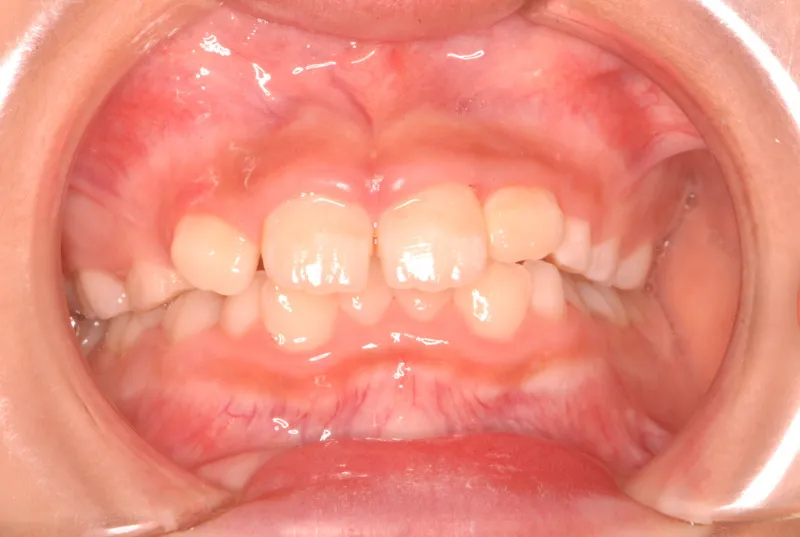

永久歯に生え変わってからはマルチブラケット装置を使用し、噛み合わせ・見た目をしっかり仕上げました。

治療回数42回、4年6ヶ月の治療期間で矯正治療を終了しました。

主訴が改善され、ご満足頂きました。

治療終了後